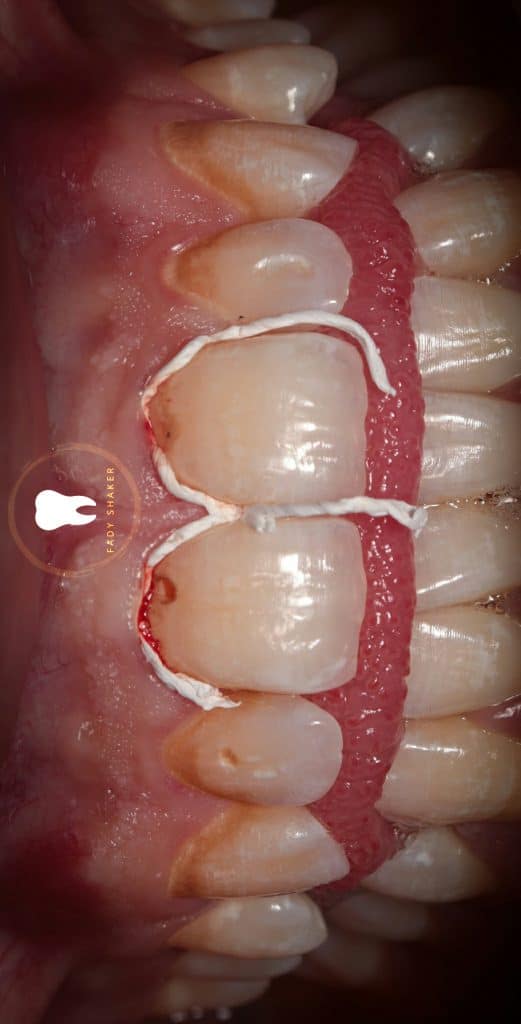

1- teflon packing in the sulcus to retract gingival tissue&expose subginigval lesion

2-apply rubberdam and secure it by clambs on #14 & #24

then i did inversion for the sheet& secure it with floss ligature

4- after that it was not enough so i use active tissue retractor clamp for further retraction

*problem: tissue retraction clamp isn’t stable

solution: use liquidam to support the clamp on canine

5-complete lesion excavation&achieve caries removal endpoint (CRE)

6-beveling the coronal margin of the cavity